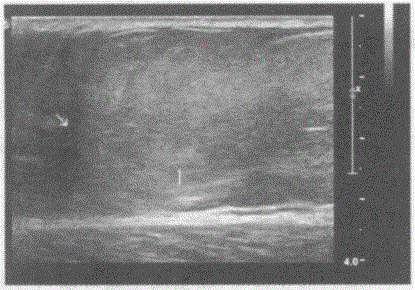

问题 临床资料:男,30岁,自诉右大腿局部肿胀,可触及一肿物。 超声综合描述:右大腿皮下可见8.0cm×6.1cm增强回声区,边界清晰,形态规则,CDFI:内未见明显动静脉血流信号。 超声提示:

选项 A.右大腿纤维瘤 B.右大腿血管瘤 C.右大腿皮下脂肪瘤 D.右大腿皮下血肿

答案 C